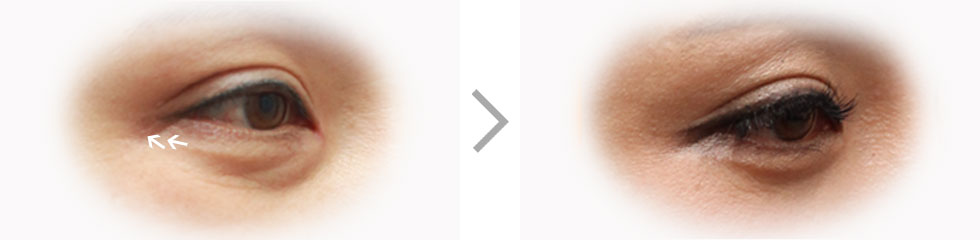

When a person ages, upper eyelid as well as lower eyelid sags and swells. Instead of simply removing such lower-eye fat, rearrangement of fat and strengthening of septum can be a better option for maintaining firmness and gives correctional effect as well.

Before Surgery

Loose skin and

protruding fat tissues

are removed or

rearrangedLoose muscles are fixed

onto periosteum to

flatten the wrinkles and

the incision is then

sutures with fine threadAfter Surgery

- Soft ImageRemoving wrinkles under the eyes as well as protruding fat layer gives softer impression to the face.

- Invisible ScarFine incision made at the eyelash makes the scar almost invisible after removing stitches

- Dark Circle ImprovementShade made by loose skin and protruding fat layers are disappeared to improve dark circles.